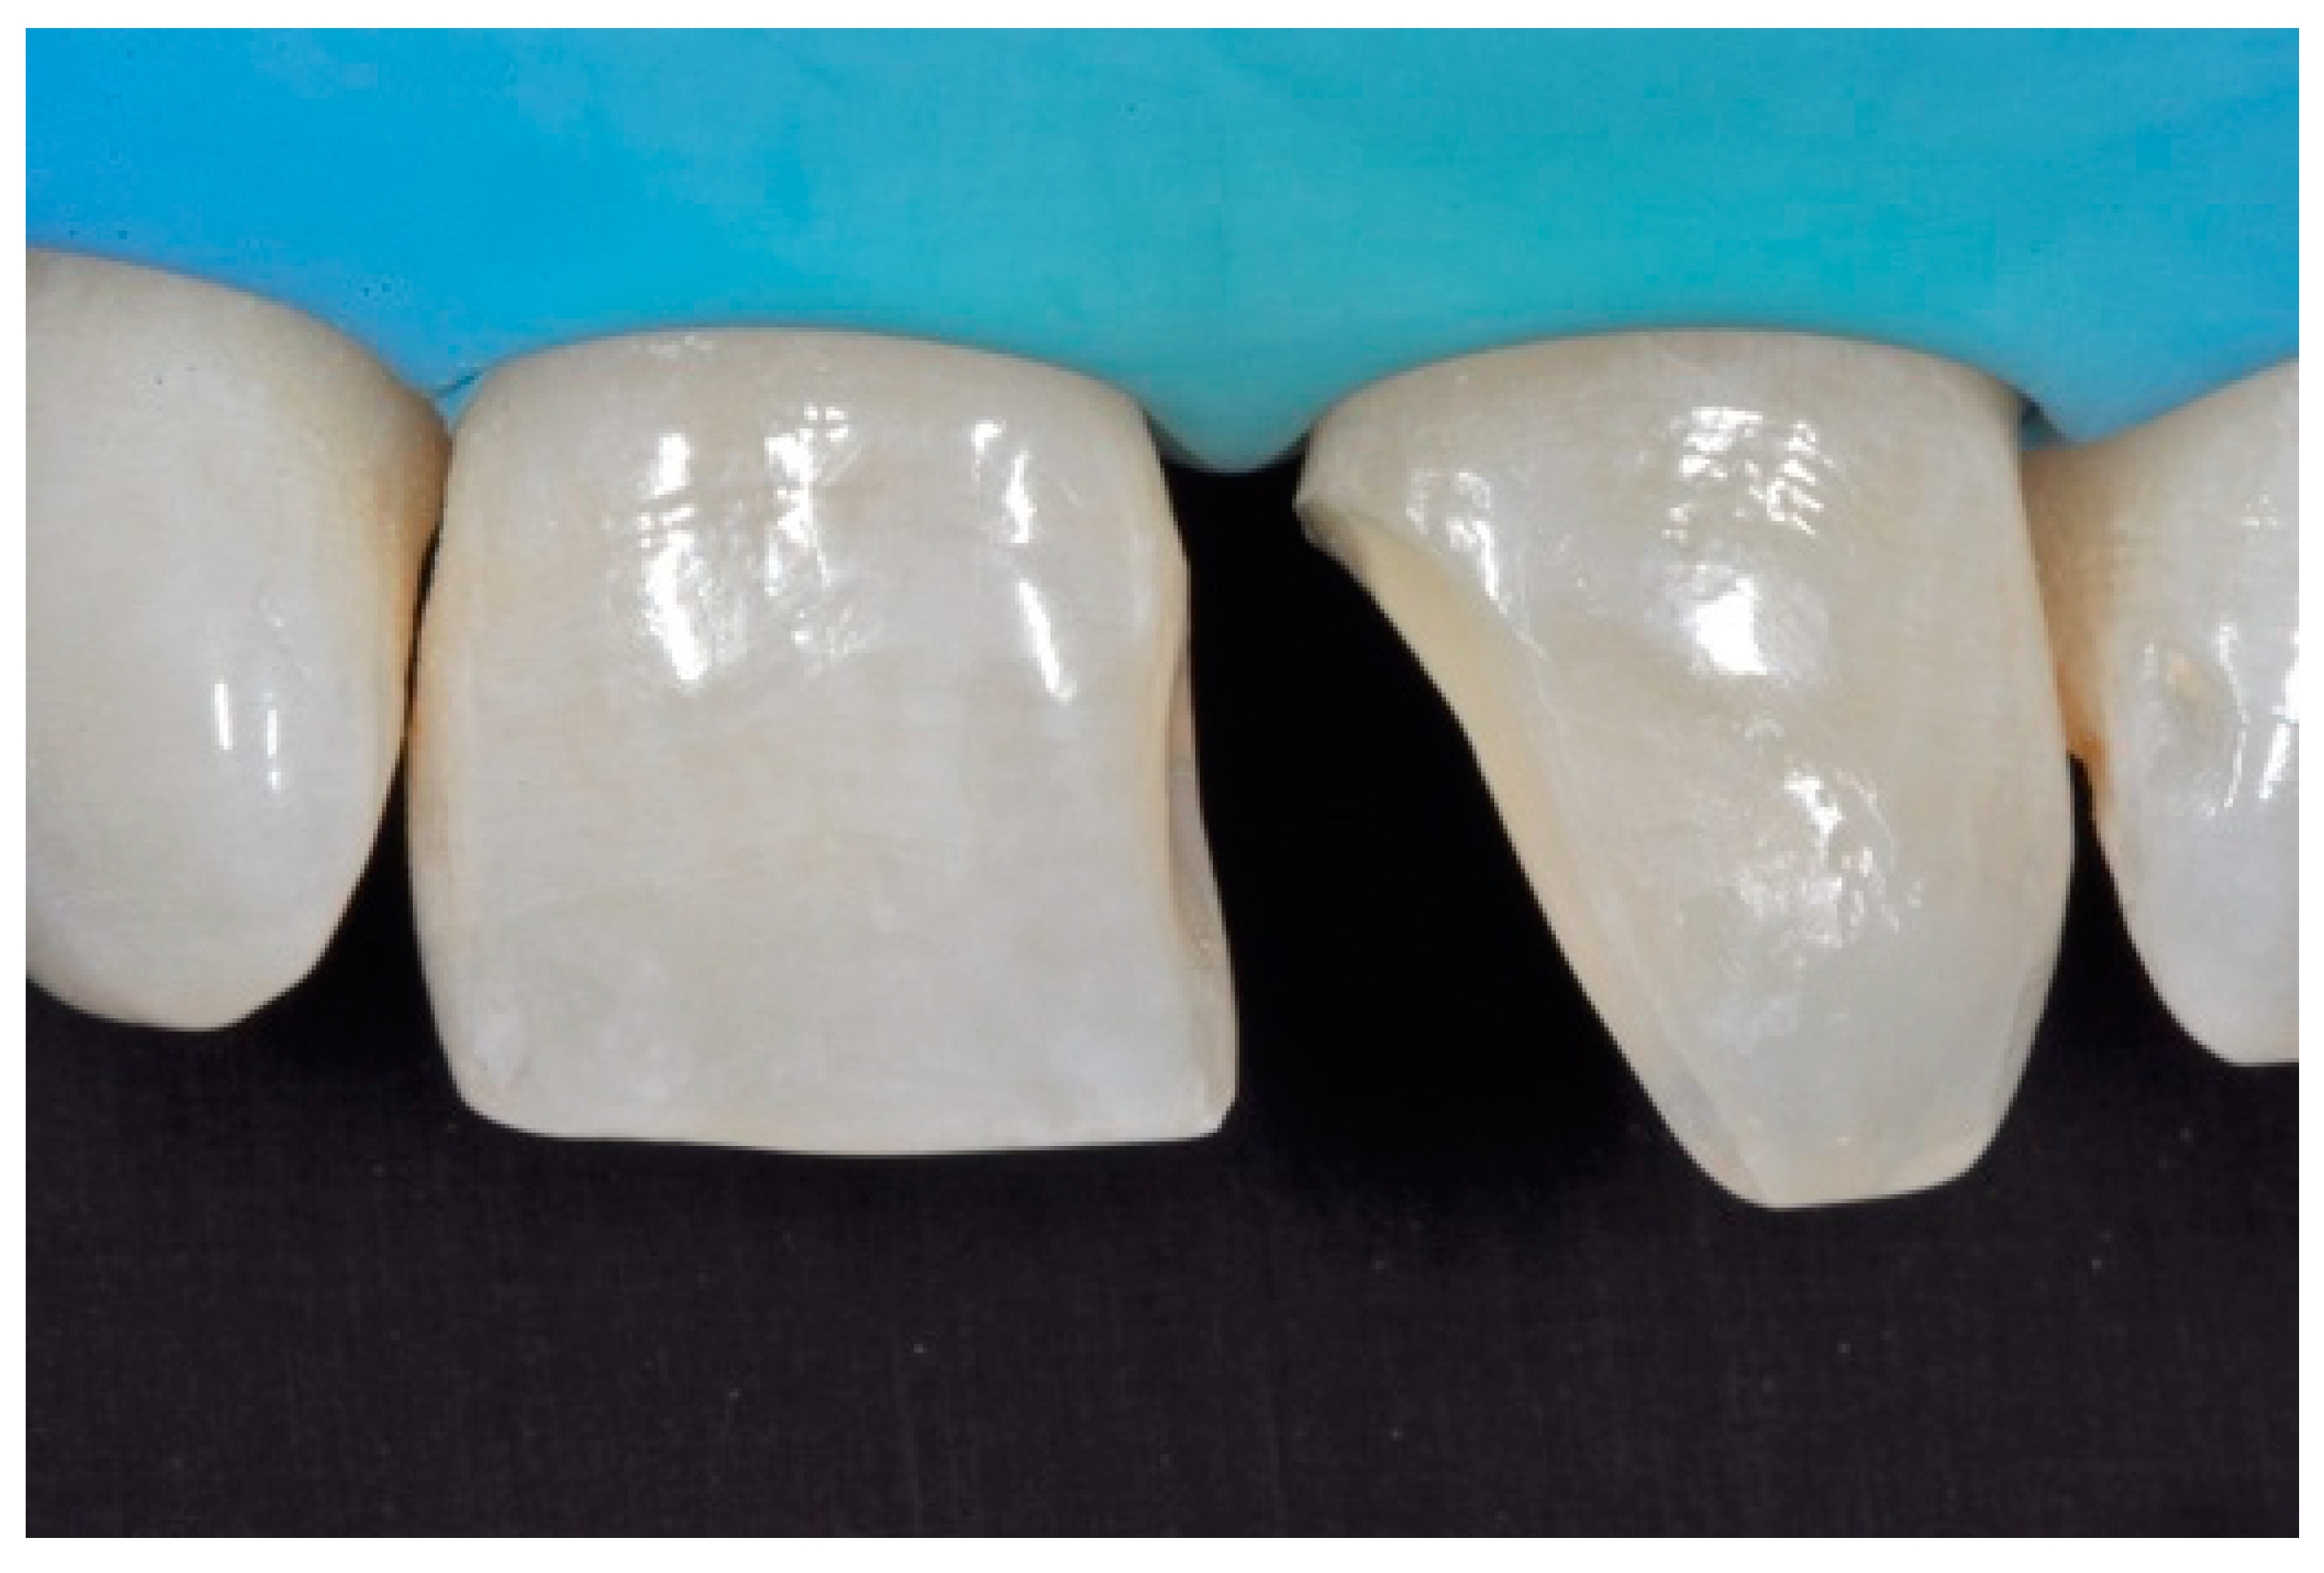

A 27-years lady presented to the dental office after traumatic accident (Figure 30). Tooth #1.1 responded positively to pulp tests (cold and electrical) while Tooth #2.1 showed pulp exposure and continuous bleeding. Endodontic treatment was therefore performed on #2.1 (Figure 31) and direct restoration of both teeth was planned. Shade was selected as described in previous case, using the button-try technique [14]. Even in this clinical case, considered the sufficient ferrule, no post was applied on Tooth #2.1. After isolation and preparation (Figure 32), adhesive procedures were performed using a self-etch two-step adhesive with selective etching procedure (Clearfil SE, Kuraray Noritake Dental, Tokyo, Japan).

Once completed, the two frames (Clearfil Majesty ES-2, A1E, A2D, Kuraray Noritake Dental, Tokyo, Japan) showed internal and external excesses that were reduced using diamond burs and discs (Figure 33 and Figure 34) strictly following the procedure described in Section 2.1.2 of present article. Excesses were removed from the distal-incisal angle of #2.1 allowing therefore to obtain the desired translucency. After silane application and bonding procedure (Figure 35) as described in Section 2.1.2, restorations were completed (Figure 36 and Figure 37). They both show satisfactory clinical integration 1.5 years post-operative (Figure 38 and Figure 39).

Figure 33.

Frame imprecisions are corrected by reducing interproximal wall from the internal side. Reprinted from Restauri diretti nei settori anteriori, G. Paolone, S. Scolavino, © 2021, with permission from Quintessence Publishing Italy.

Figure 34.

Frame is also trimmed reducing external outline. Reprinted from Restauri diretti nei settori anteriori, G. Paolone, S. Scolavino, © 2021, with permission from Quintessence Publishing Italy.